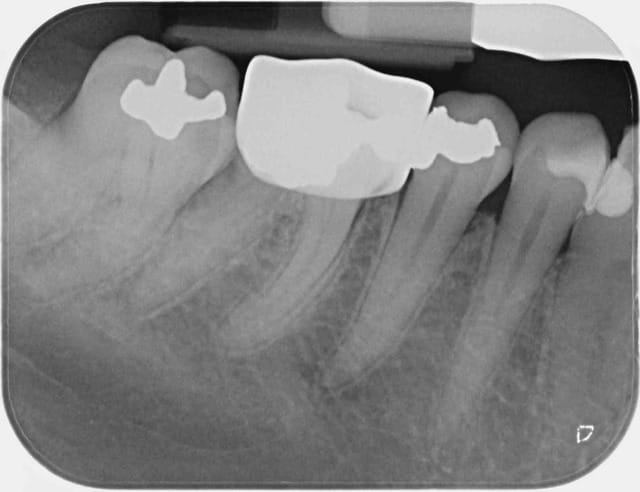

Ce message n'apporte rien au débat, c'est juste pour parler de cette patiente qui n'avait pas donné suite au devis pour couronner la 46. Au contrôle annuel suivant, la dent était couronnée, tout allait bien. Il a fallu que je lui pose la question pour qu'elle m'explique, sans la moindre gêne, que sa mutuelle GROUPAMA l'avait orientée vers un dentiste partenaire "moins cher".

Rien que sur la radio, je vous laisse admirer la qualité de la morphologie occlusale, le profil d'émergence, les points de contact (ou leur absence)... Je n'ai pas osé prendre de photo de ce blockhaus.

Bref, un an après, voici que la patiente revient pour me dire que la couronne ne va pas du tout, que ça la gêne.

Je me suis donc fait un malin plaisir de la renvoyer vers ce con-frère,

ET CA FAIT DU BIENNNNNNNNNNNNNN.